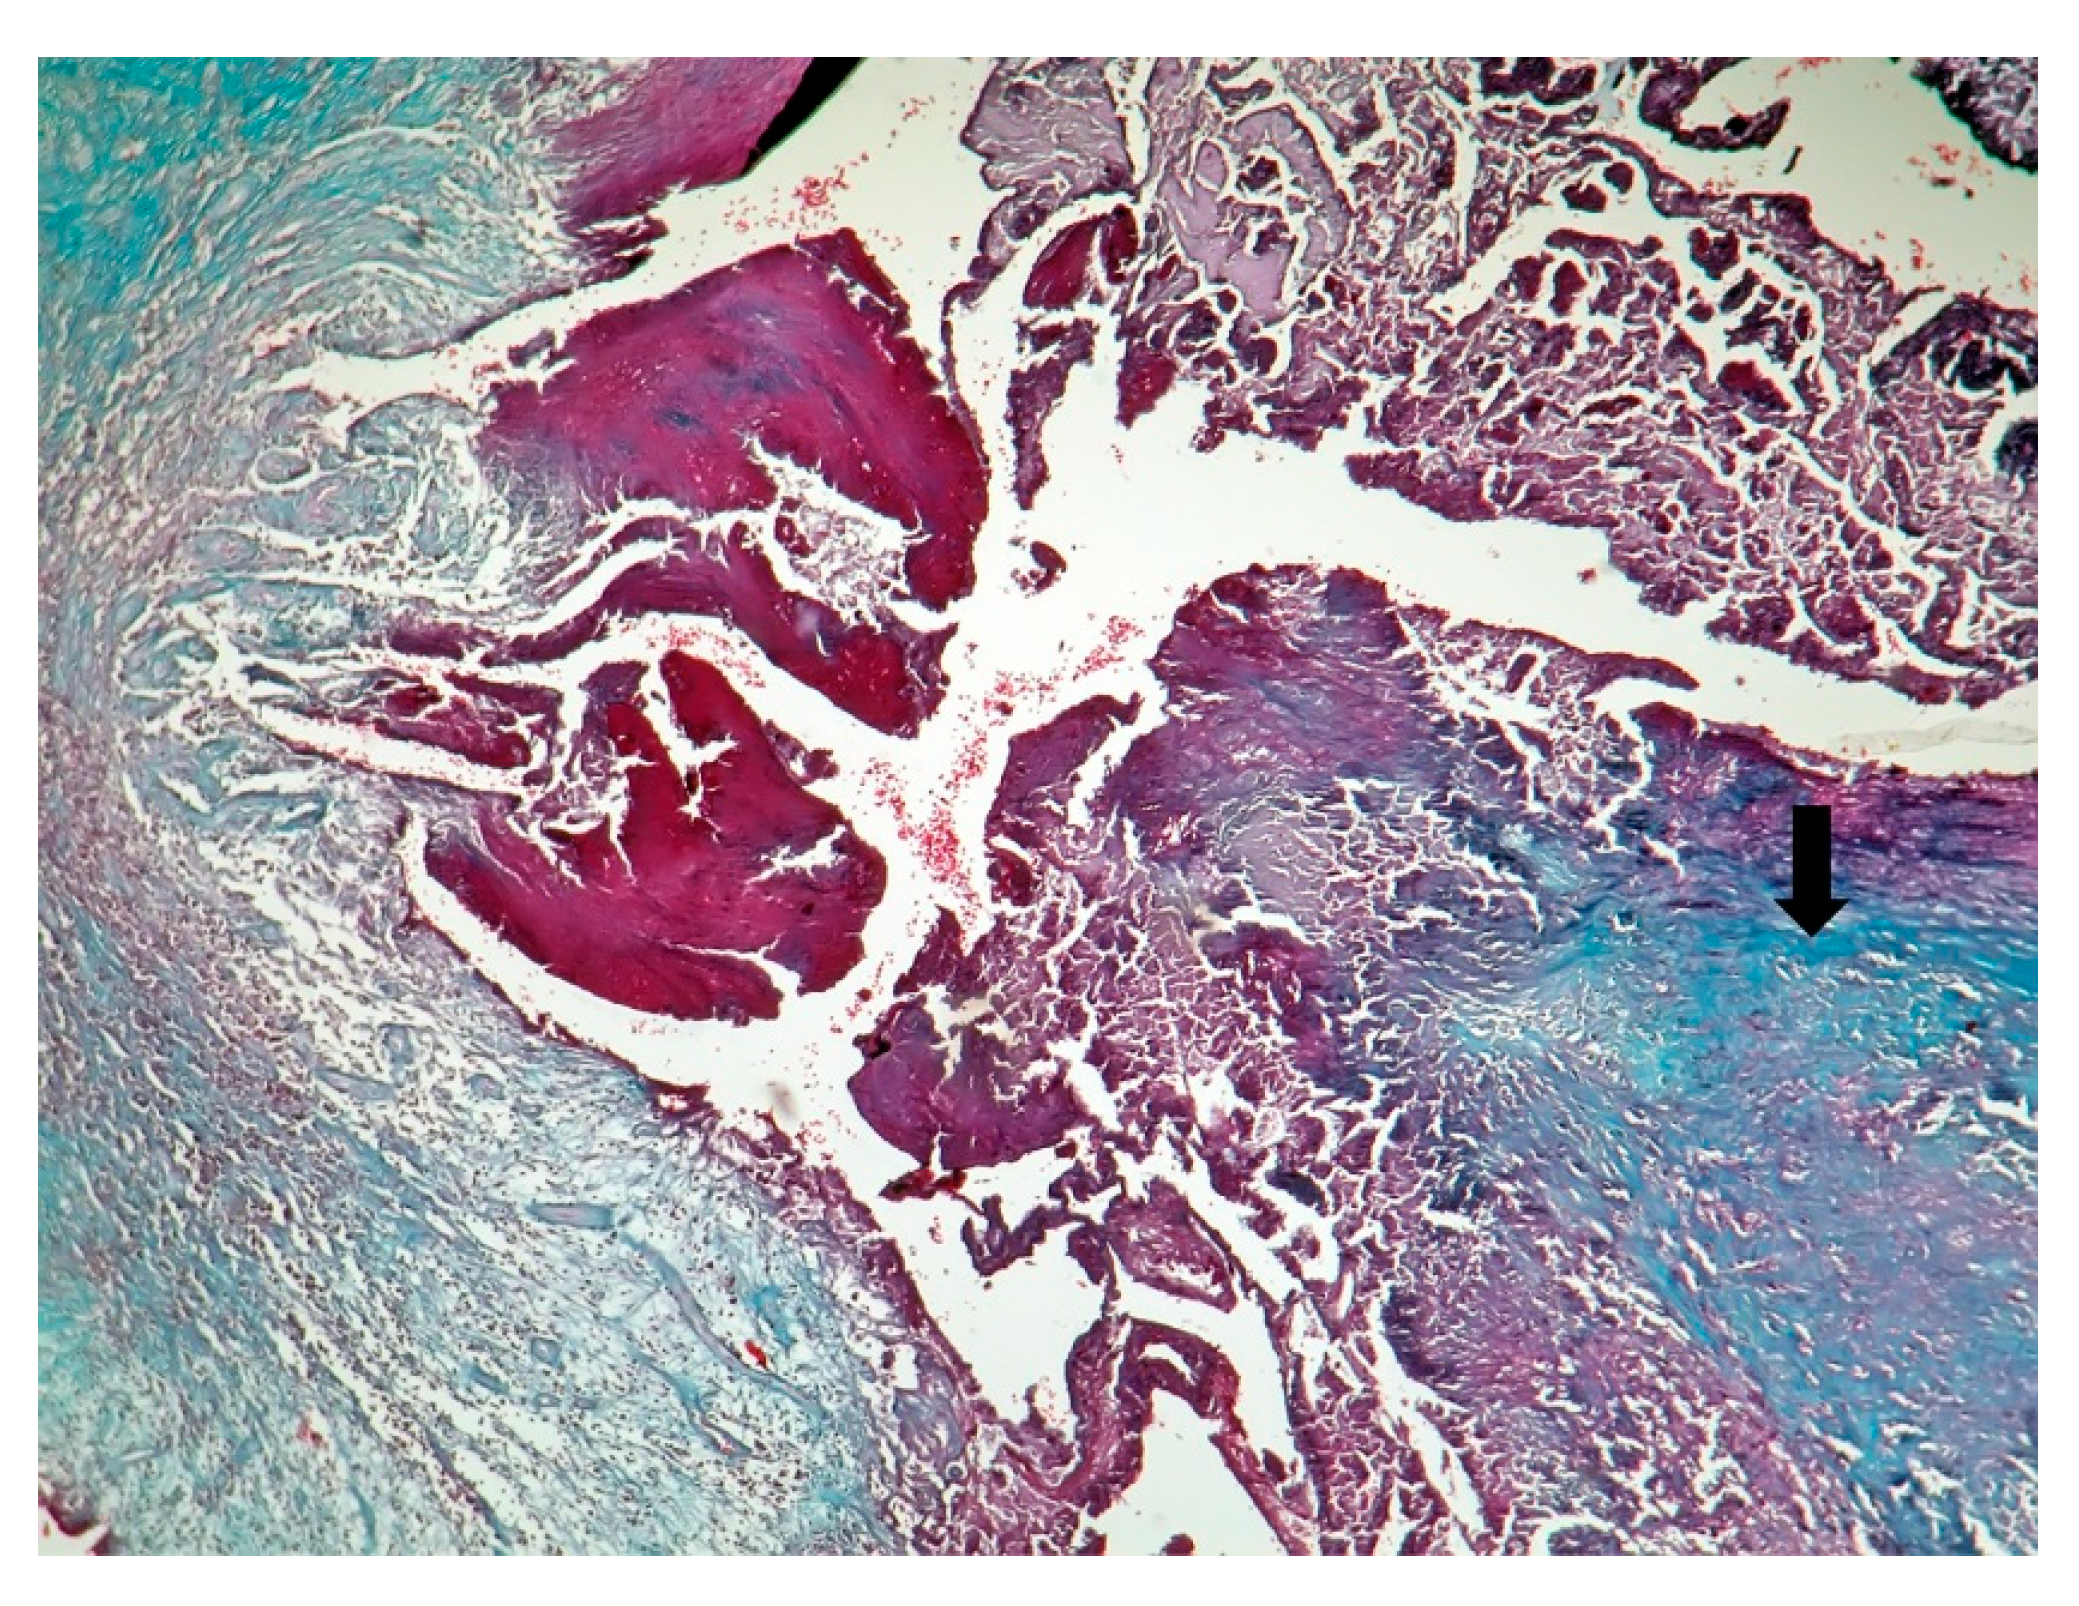

| Macroscopic | Mural trombi, Endocardial fibrosis [23] Monovalvular involvement Mixoid degeneration Valve ulceration or fibrinous mass No fibrin valve deposits [24,25] | Small, warty, sessile vegetations on valve flow surface [26] | Large or small vegetations on valve flow surface [27] | Small or absent vegetations, with a smooth nodular aspect [13] |

| Microscopic | Mixoid degeneration, mixed inflammatory pattern, granulomas, thickening of the small vessels wall [23] | Platelets, fibrin, red blood cells Repetitive process with fibroblastic organization and neovascularization [28] | Fibrin, polymorphonuclear inflammation and some bacterial colonies [29] | Minimal mononuclear inflammation, histiocytes, foamy macrophages and mild vascularization [30] Granulomas [31] Microabscesses; usually no microorganism, sometimes coccoid inclusions [23] Fibrosis, thrombosis and calcifications, mimicking degenerative damage [32] |

| Predilection | Right heart [13] | Mitral, aortic, tricuspid valves [27] | Aortic, mitral valve [33] | Aortic, mitral valves [32] |

| Mechanism | Vasculitis, endothelial cells disruption, thrombo-inflammation, fibrinogen oxidation, hypercoagulability, APS induction, hyperhomocysteinemia, deficient fibrinolysis [34] | Valve endothelium initially normal [25] Fibrin-platelet, red blood cells thrombi [28] | Fibronectin adherence [35] | Vasculitis, APS induction [36] |